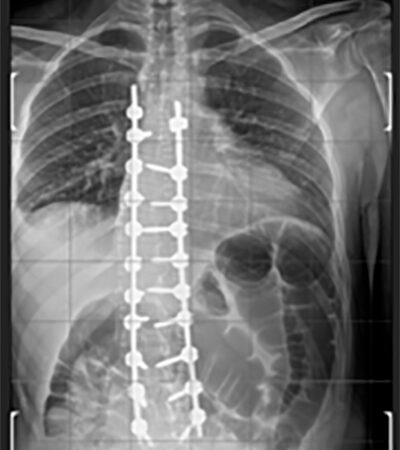

Artrodesi dorso lombare con osteotomie correttive

Radiografia della colonna in toto post-operatoria